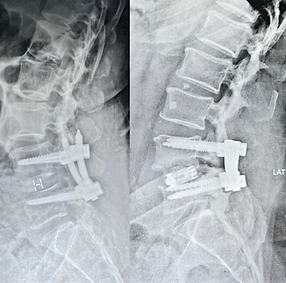

الدكتور غزوان حسن جراح عظام متخصص في جراحة العمود الفقري، ويُركز على الجراحة طفيفة التوغل والجراحة التنظيرية. يُقيم في بغداد، ويجمع بين التدريب الدولي والتقنيات الجراحية المتقدمة والمشاركة الأكاديم ية لتقديم رعاية حديثة قائمة على الأدلة في مجال جراحة العمود الفقري، مع التركيز على سلامة المريض، وسرعة التعافي، والنتائج طويلة الأمد.

مع التركيز الشديد على التقنيات طفيفة التوغل والتنظير الداخلي، نهدف إلى تقليل تلف الأنسجة، وتسريع الشفاء، وتحسين النتائج على المدى الطويل. تُصمم كل خطة علاجية بعناية فائقة لتناسب كل مريض على حدة، حيث ندمج الخبرة السريرية مع التكنولوجيا الحديثة لضمان أعلى معايير الرعاية.